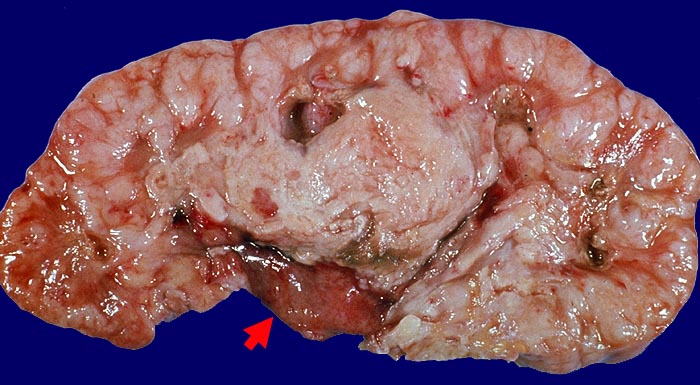

PathoPic ID 1589 - Analgetika-Nephropathie: Nierenbeckenkarzinom.

Analgetika-Nephropathie: Nierenbeckenkarzinom.

maligner Tumor

Niere

Das Nierenbeckenkarzinom hat die gesamte Niere diffus durchsetzt. Braunverfärbung der

►

Nierenbeckenschleimhaut.

Makroskopie

52